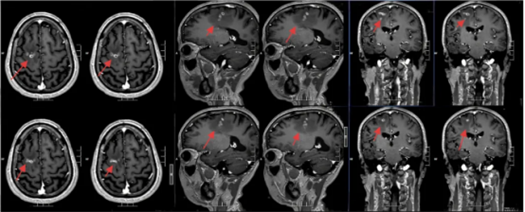

该院神经外二科张旭标副主任医师接诊后,根据影像结果,发现其右额叶病变,局部肉芽肿形成伴周围组织水肿。“这是大脑为了隔离‘入侵者’筑起一道‘隔离墙’,周围的脑组织被刺激得肿胀。”张旭标解释,这些影像特征高度指向脑裂头蚴病。经比对,病灶范围稳定,手术时机成熟。

术前影像